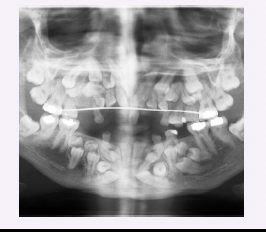

Cherubism

● Genetic disorder that typically appears between ages 2 – 5, with progression during childhood and

stabilization or regression after puberty

● Multilocular, bilateral, radiolucent (“soap bubble”) lesions in the mandible and sometimes the maxilla

● Jaw expansion leads to facial swelling and can cause tooth displacement, malocclusion, and delayed

eruption of teeth

● Lesions are histologically identical to those of a central giant cell granuloma